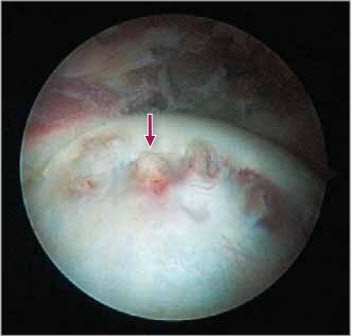

Offset-Störung

5 Intraoperative Aufnahme (Arthroskopie) mit ausgeprägter Offset-Störung (metaphysäre Vorwölbung am Kopf-Hals-Übergang) bei Epiphysiolysis capitis femoris. Diese Vorwölbung mit Ostoephyten (Pfeil) wird intraoperativ arthroskopisch abgetragen

Minimal-invasive Operationstechnik

Dank der grossen Fortschritte, die auf dem Gebiet der arthroskopischen Hüftchirurgie (Hüftspiegelung) stattfanden, wird in der Schulthess Klinik in Zusammenarbeit mit unserem Hüftspezialisten PD Dr. med. M. Leunig (Chefarzt Untere Extremität) die minimal-invasive arthroskopische Abtragung der metaphysären Vorwölbung mit der percutanen In-situ-Fixation des Hüftkopfs mit einer zentralen Schraube kombiniert (Abb. 5, 6, 7). Diese neue Operationstechnik erlaubt die Wiederherstellung einer normalen Hüftmechanik und ist mit der kleinsten Morbidität verbunden.